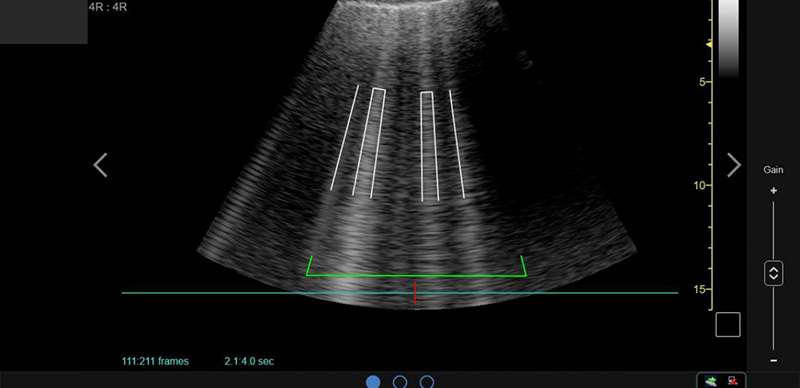

Ultrasound is often associated with childbirth — it often gives expectant parents the first glance of their new child in utero — but in 2020 the versatile imaging technology has taken on a crucial new role: helping clinicians as they battle the coronavirus pandemic. Ultrasound machines, which see inside the body by emitting and then recording the echoes of high-frequency soundwaves, enable doctors to get a glimpse of the tell-tale lesions that COVID-19 leaves in the lungs, allowing them to quickly make triage decisions. “I joke with medical students and residents that although we carry a stethoscope, anything I really want to find out, I can see with an ultrasound,” Dr. Brian Boer, a critical care and pulmonary disease specialist at the University of Nebraska Medical Center, told Intel, which recently published a report about its collaboration with GE Healthcare. Intel’s chips and other tools play an important role because they help GE add artificial intelligence to its latest ultrasound machines.

Scanning smartly: The algorithms available on GE Healthcare’s Venue and Venue Go machines have been trained on hundreds of thousands of ultrasound images, so they can automatically detect irregularities and giveaway patterns in grayscale and highlight them for clinicians. Ultrasound can be also conducted at the bedside, on portable machines that can be cleaned and sanitized quickly between patients. GE Healthcare’s ultrasound machines leverage computing power from Intel, just like the company’s smart X-rays rely on Intel processors.